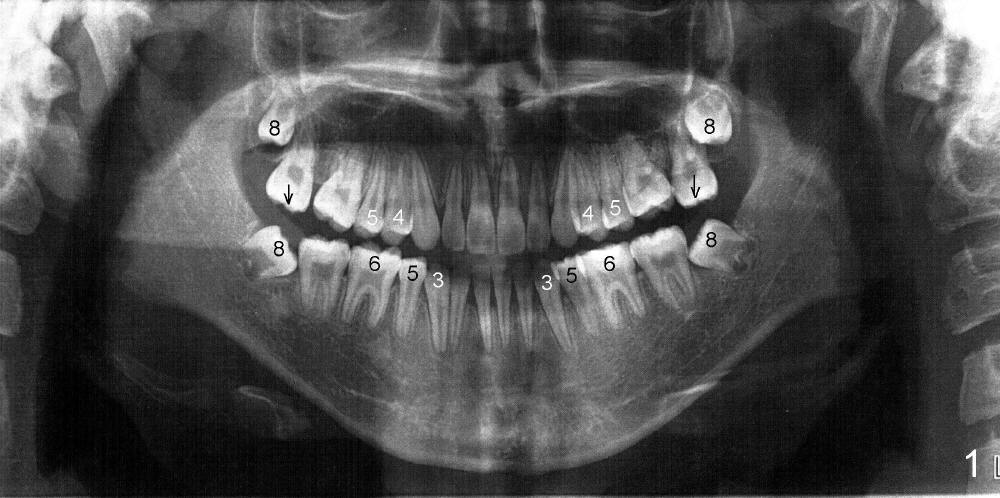

全景片分析表明(图一):下颌第三磨牙近中阻生,似乎非拔不可,而上颌智齿位置太高,拔除非常困难,告诉病人妈妈,她好像讽刺地说口外医生常规拔除四个智齿,为什么你不行?心平气和地解释专家有时也下不了手术台,拔除上颌智齿可能弊大于利,今天先拔除下颌智齿,如果时间充裕,再决定是否拔除上颌智齿,妈妈同意。

全景片还显示下颌减数矫正(少两个双尖牙),原来病人以前前牙反合,矫正后前牙第一类咬合,所以面部侧面观尚属正常,而后牙仍是第三类,所以上颌第二磨牙没有咬合功能,往下面延伸(箭头),所以现在不拔上颌智齿没多大问题。这时问妈妈为什么当时不选择正合治疗(orthognathic

打完下颌神经麻药,乘麻药还没有奏效,拍摄图二至图五,图二,图三显示前牙第一类咬合,而后牙第三类,上颌第二磨牙(7)咬在下颌牙龈(*,仿佛形成白斑(leukoplakia))。图四,图五显示上颌第二磨牙向下伸长。那时我还不具有力挽狂澜能力。那么这四个智齿该拔吗?